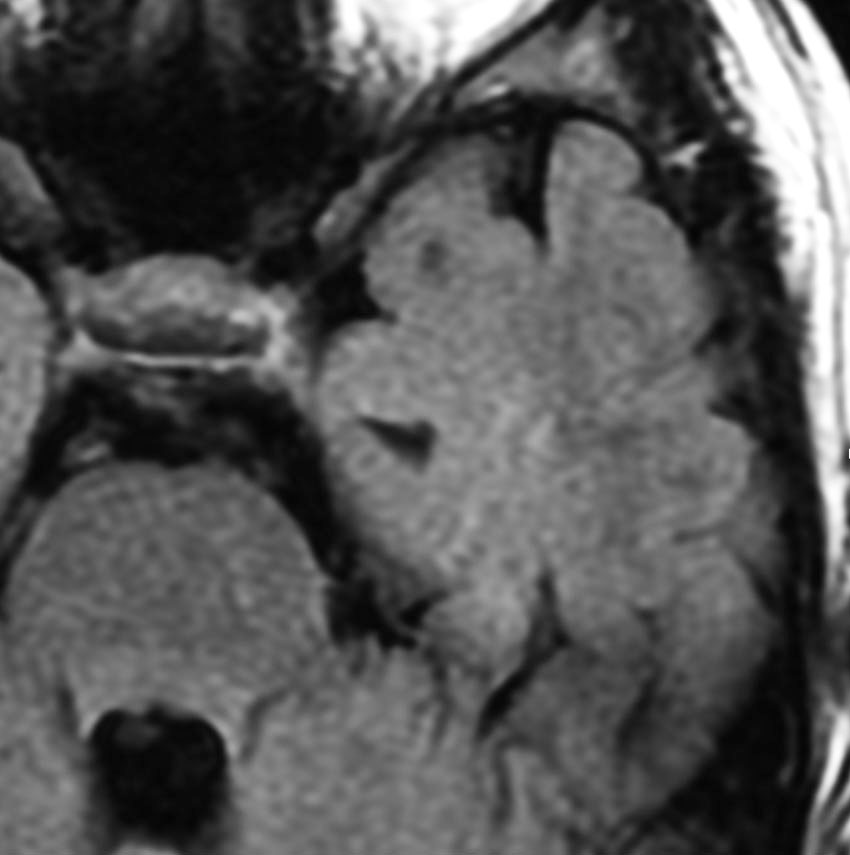

60代の女性に無症候で発見された稀な部位のPXA。結節様ですが脳とのはっきりした境はなく,多房性ののう胞を伴っていました。T2とFLAIR像ではわずかな浸潤像あるいは腫瘍周辺浮腫が疑われます。PXAに特徴的な画像ですが,大脳深部発生でもあり,PXAと画像診断することはできません。定位脳生検術 MRI-guided sterotactic biopsyで病理組織診断を行ない経過観察しました。

3年観察したら嚢胞を伴って増大しました。幸いのう胞性拡大が脳表方向であったのでparietal transcortical approachで全摘出できました。側脳室三角部腫瘍への到達法と同じアプローチですが,この経路では頭頂葉症候を後遺することがありません。